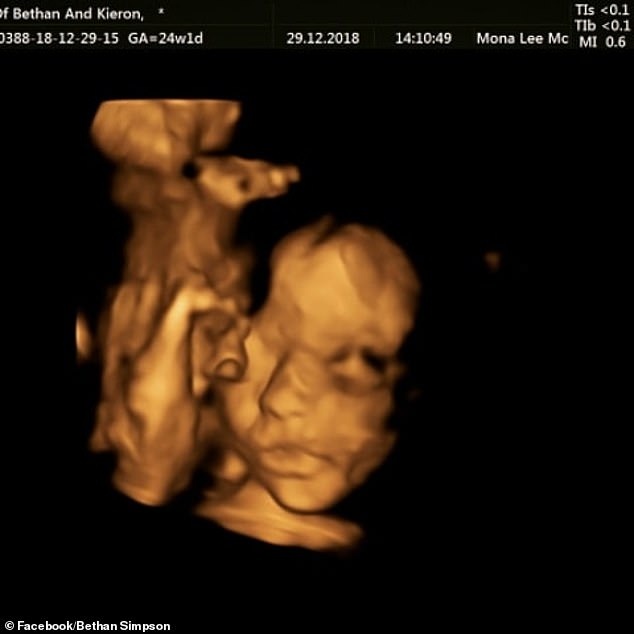

| Hình ảnh siêu âm ở tuần thứ 20 cho thấy kích thước đầu của thai nhi không bình thường. Ảnh: Dailymail. |

Tới tuần thứ 24 của thai kỳ, Bethan được phẫu thuật để điều trị tật nứt đốt sống cho thai nhi. Ca phẫu thuật diễn ra thành công, tình trạng của thai nhi và mẹ bình thường, dự kiến cô sẽ sinh bé gái vào tháng 4 tới.